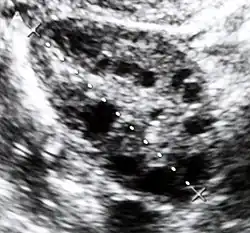

Ultrasound of a polycystic ovary. Each of the dark circles represents a fluid-filled cyst.

Polycystic ovary syndrome (PCOS) is an endocrine disorder characterized by an excess of androgens produced by the ovaries. It is estimated that approximately 90% of women with PCOS demonstrate hypersecretion of these hormones.[19] The cause of this condition is unknown. Speculations include genetic predisposition; however, the gene or genes responsible for this remain unidentified.[20] The condition may have a hereditary basis. Other possible causes include elevated insulin production. Most cases of PCOS involve insulin resistance.[21] It is thought that adipose tissue dysfunction plays a role in the insulin resistance seen in PCOS.[21] Insulin can induce excess testosterone secretion from the ovaries.[22] A complication associated with polycystic ovary syndrome is high cholesterol, which is treated with statins. In a meta-analysis, atorvastatin was shown to decrease androgen concentrations in people with hyperandrogenism.[23]